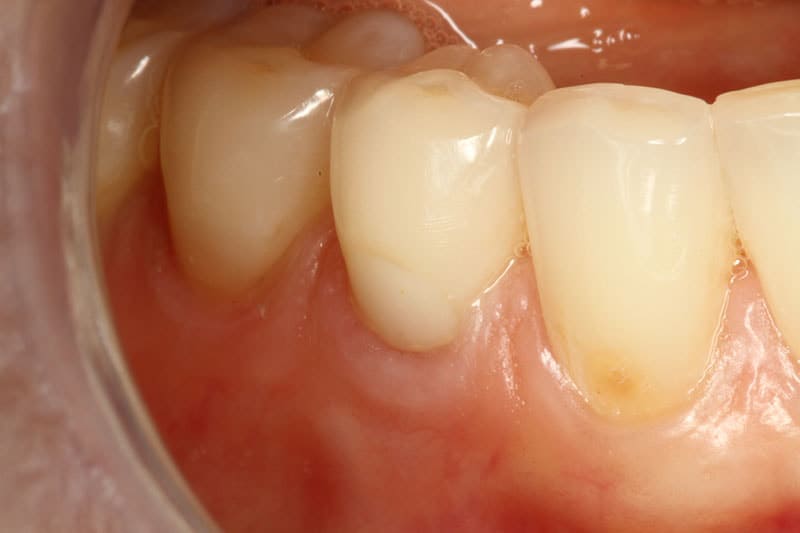

Before